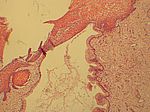

Plattenepithelmetaplasie Cervix, HE